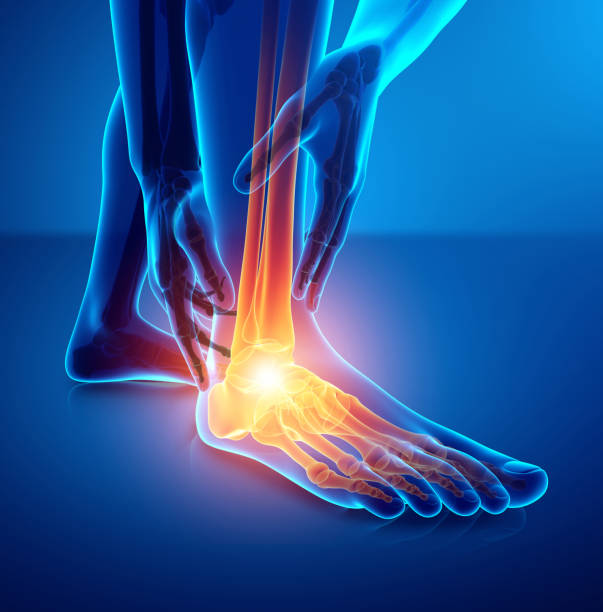

발뒤꿈치 통증의 두 번째 원인은 아킬레스건염입니다. 아킬레스건염은 아킬레스건에 반복되는 고통스럽고 미세한 손상으로 인해 발뒤꿈치 통증을 유발하게 되는 질환입니다. 통증은 주로 발뒤꿈치나 발바닥에 나타나며 특히 아킬레스건 부위에 붓고 격렬한 운동 후에는 종아리부터 발뒤꿈치까지 심한 통증이 나타납니다. 이러한 증상이 지속되면 통증이 고관절, 엉덩이와 등에도 무리가 갈 수 있어 다른 질환과 마찬가지로 빠른 치료가 중요합니다.